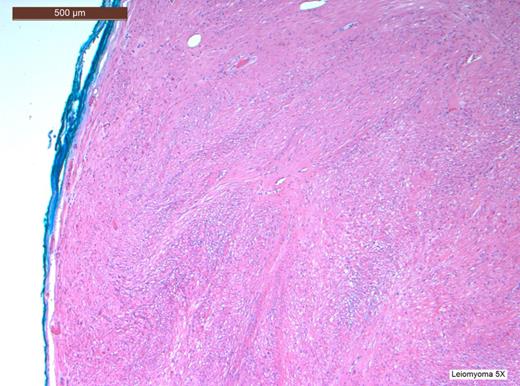

Histopathological analysis of the lesion, including immunohistochemical profiling, revealed a well-circumscribed nodular tumour composed of smooth muscle cells with eosinophilic cytoplasm and spindle-shaped nuclei. The cells were arranged in interlacing fascicles with evidence of perinuclear vacuoles using haematoxylin and eosin staining. There was no evidence of necrosis, mitosis or significant nuclear pleomorphism. The specimen was negative for CD117 staining, hence excluding the possibility of a gastrointestinal stromal tumour. It was also negative for S100. However, stain was positive for smooth muscle actin (SMA) and desmin, which confirmed that specimen was of muscular origin. The histology therefore identified the lesion as a leiomyoma (Figs 2–6).

CD117 staining is negative hence excluding any possibility that this was a gastrointestinal stromal tumour (GIST).